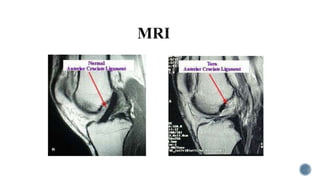

Imaging Studies:

• MRI

 90-98% sensitivity.

 Can identify bone bruising.

 Gold standard

Imaging Studies: • MRI 90-98% sensitivity.  Can identify bone bruising.  Gold standard • Plain X ray - Usually normal ,but may show tibial spine avulsion if present • Arthrograms – (X ray of a joint after contrast medium is injected ) • Replaced by MRI Arthroscopy